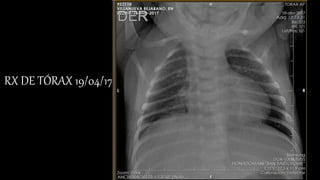

RX DE TÓRAX 19/04/17

RX DE TÓRAX19/04/17